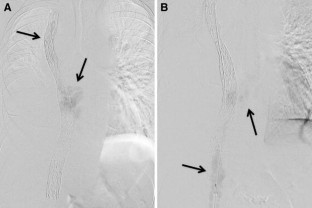

Fig. 1